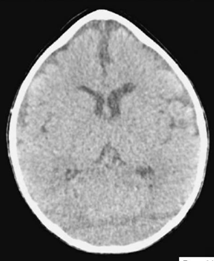

Рис. №2 а) – вариант нормы

б) – деформация черепа вызванная синостозом (слиянием) лямбдовидного шва слева, указателем показаны множественные пальцевые вдавления (истончение костной ткани, вплоть до появление «дыр»).